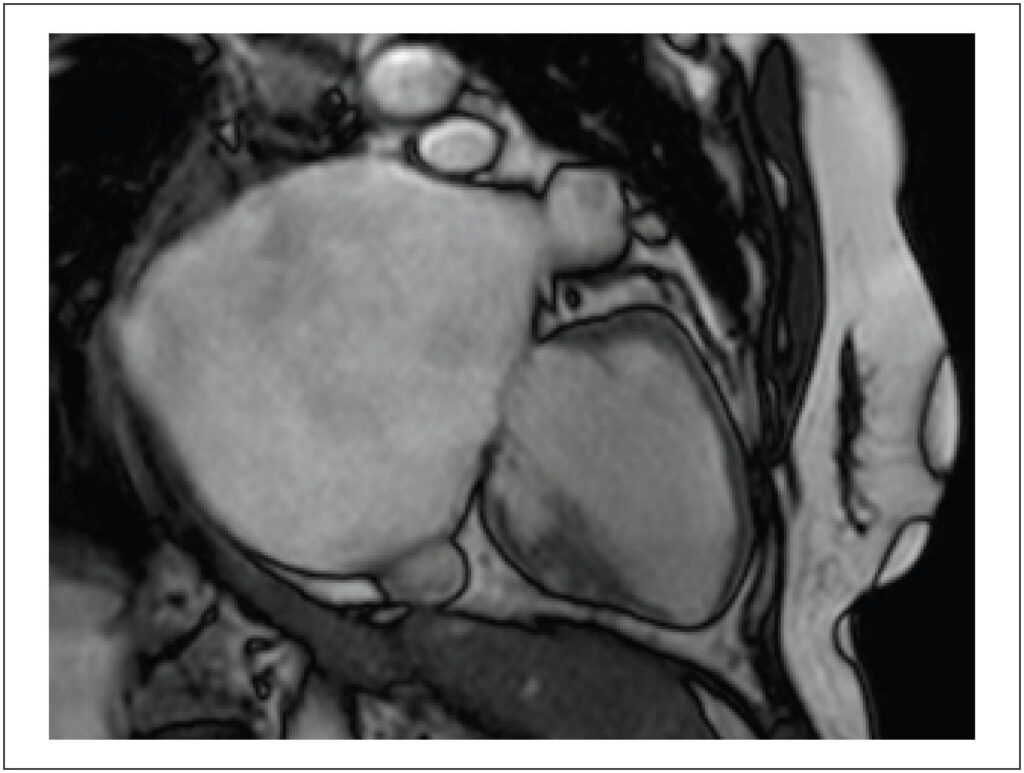

Átrio Esquerdo Gigante em Doença Valvar Mitral Reumática

O Átrio Esquerdo Gigante (AEG) é uma condição rara e mais comumente relacionada à doença valvar mitral reumática; pode ser confundido com alguns possíveis diagnósticos diferenciais quando ferramentas pouco acuradas são implementadas na sua investigação, podendo acarretar procedimentos desnecessários e particularmente perigosos neste cenário. Métodos de imagem cardíaca, tais como a Ressonância Magnética Cardíaca (RMC) podem ser úteis nesta diferenciação por sua alta resolução espacial, possibilitando tanto o diagnóstico, como a programação da intervenção cirúrgica, caso indicada. A solicitação do método diagnóstico mais acertado, entretanto, requer conhecimento sobre esta condição, levando à sua correta suspeição. Além disso, a escolha pela volumetria em lugar do método biplanar na RMC em casos de grande deformação atrial é mais uma forma de assegurar a acurácia dos valores obtidos.